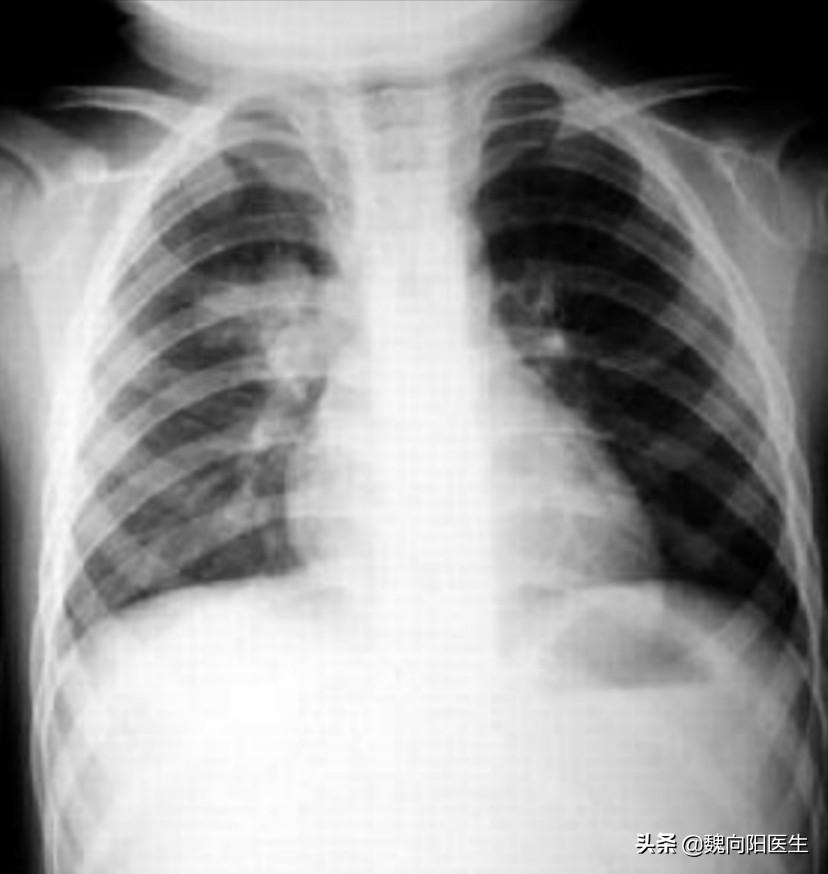

也不是所有的肺炎都会出现肺部的异常呼吸音(湿罗音和干罗音)。必要的时候的时候也需要查胸片或者胸部CT!